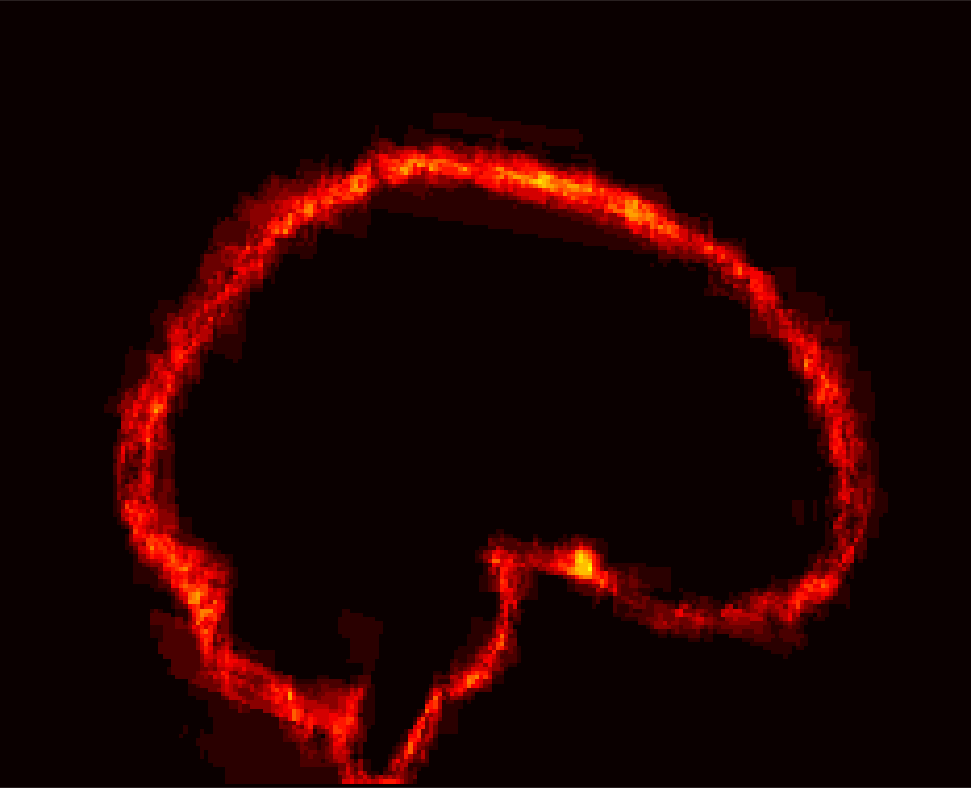

[Uncaptioned image] [Uncaptioned image] [Uncaptioned image] [Uncaptioned image]

(a) (b) (c) (d)

Figure 8: Example BRATS image with its decomposition result in atlas space. (a) Input image after pre-processing; (b) quasi-normal image L+M𝐿𝑀L+M; (c) non-brain image S𝑆S; (d) pathology image T𝑇T.

In addition to extracting the brain from pathological datasets, our method also allows for the estimation of a corresponding quasi-normal image in atlas space, although this is not the main goal of this paper. Fig.8 shows an example of the reconstructed quasi-normal image (L𝐿L) for an image of the BRATS dataset, as well as an estimation of the pathology (pathology image T𝑇T and non-brain image S𝑆S). Compared to the original image, the pathology shown in the quasi-normal image has been greatly reduced. Hence this image can be used for the registration with a normal image or a normal atlas. This has been shown to improve registration accuracy for the registration of pathological images [27]. Furthermore, an estimate of the pathology (here a tumor) is also obtained which may be useful for further analysis. Note that in this example image the total variation term captures more than just the tumor. This may be due to inconsistencies in the image appearance between the normal images (obtained from OASIS data) and the test dataset. As our goal is atlas alignment rather than quasi-normal image reconstruction or pathology segmentation, such a decomposition is acceptable, although we could improve this by tuning the parameters or applying regularization steps as in [27].